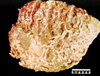

Pathogenesis (img)

Grain overload, rumenal acidosis, mucosal damage, opportunistic fungal infection, vasculitis, ischemia and mucosal ulceration